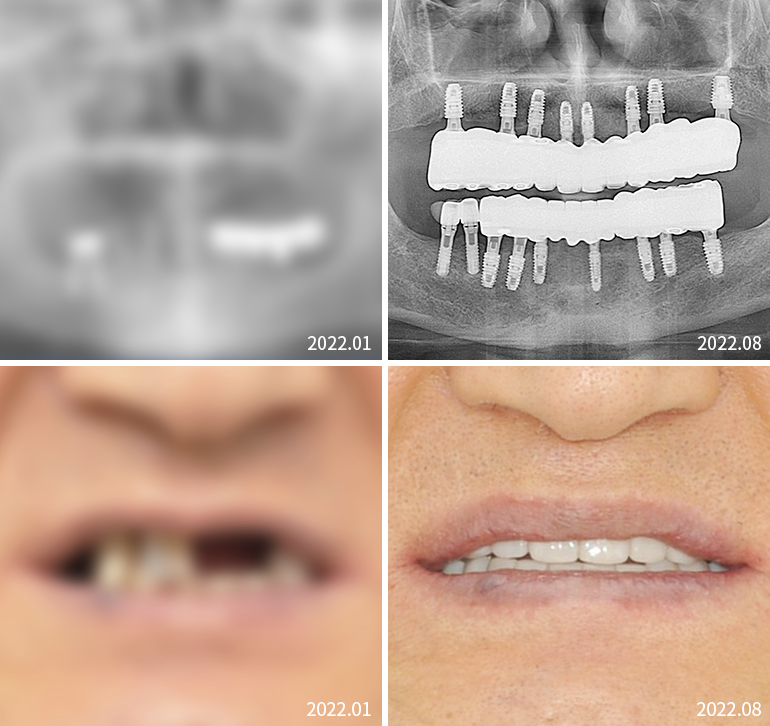

전체임플란트